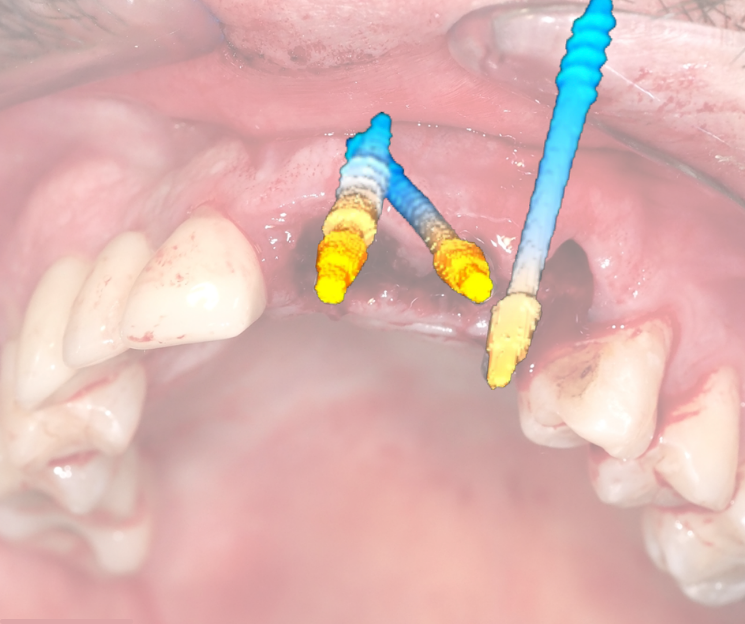

Extracción de piezas 21, 22 y 23 con infección activa

Paciente con infecciones de origen dental que comprometían severamente el hueso alveolar en la zona anterior superior. Se realizó la extracción de los dientes 21, 22 y 23, y se optó por una rehabilitación inmediata mediante implantes córticobasales.

Estrategia protésica e implantes utilizados:

- 1 implante córticobasal compresivo

- 2 implantes córticobasales rectos y finos

Esta combinación permitió anclar los implantes en hueso cortical, que mantiene su estabilidad incluso en presencia de procesos infecciosos en el hueso alveolar. El resultado: rehabilitación funcional y estética el mismo día de la cirugía.